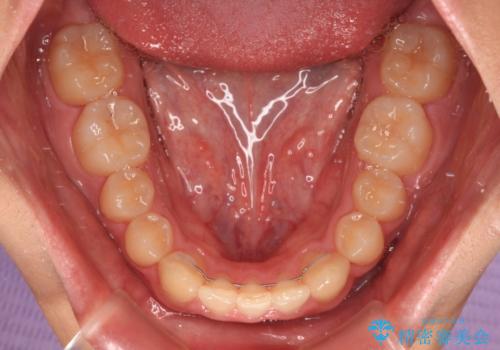

下顎前歯が一本欠損しており、下顎の歯列が小さいため、ディープバイトになりやすい状態でした。

傾斜しいている大臼歯を立ち上げながら、下顎歯列を上顎に対して前方位となるように工夫し、デコボコを解消した上でディープバイトも改善することができました。